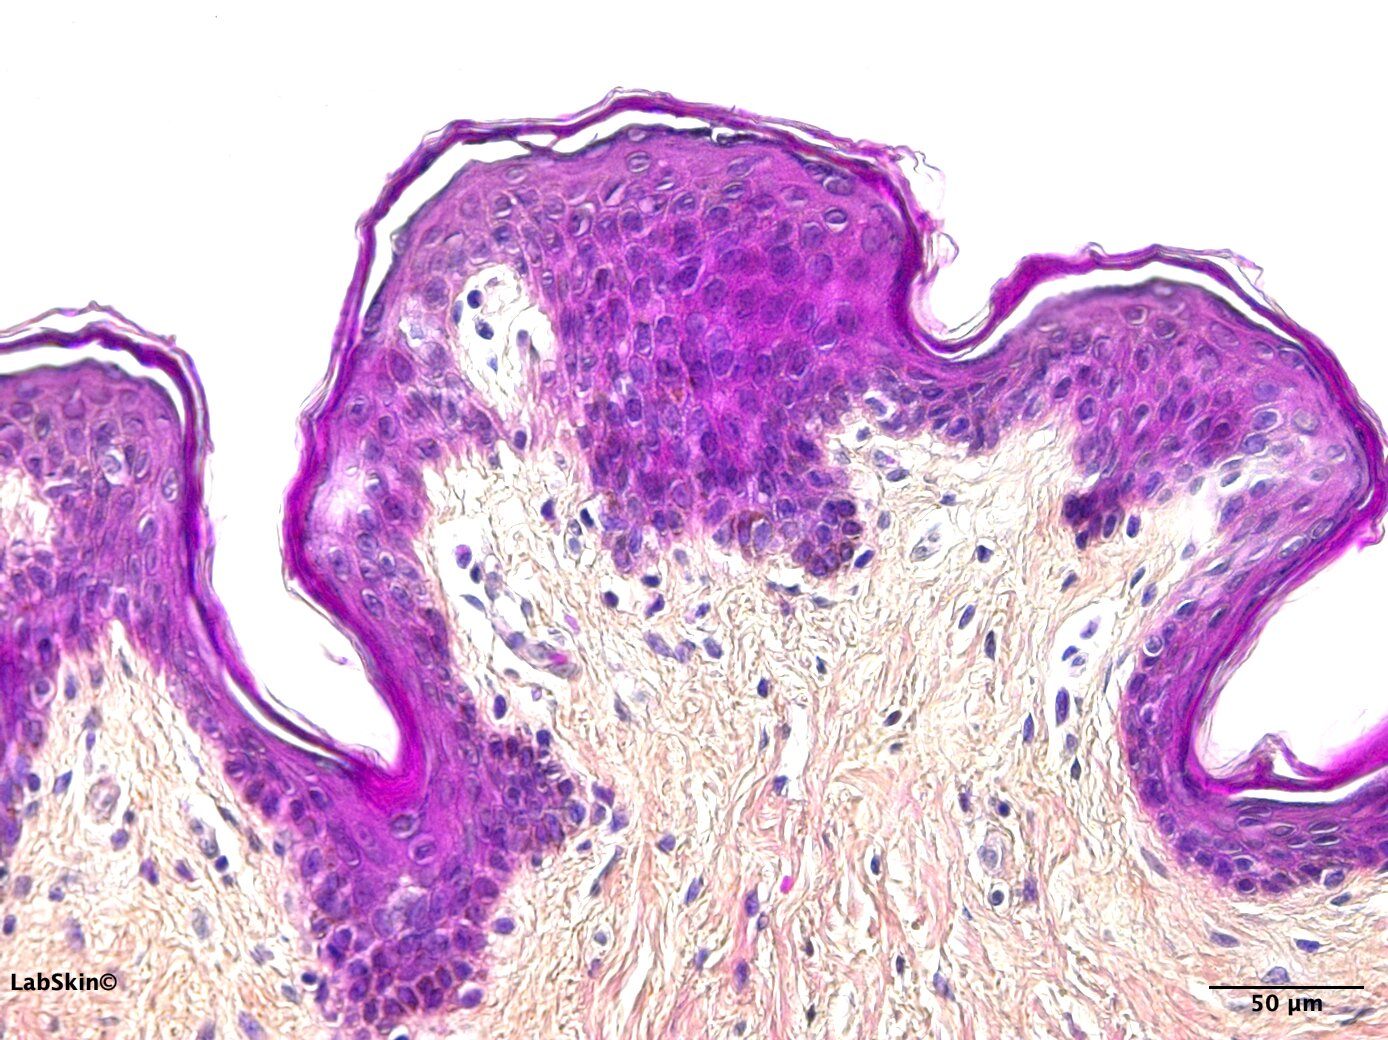

3D SKIN EQUIVALENT

Reconstructed epidermis